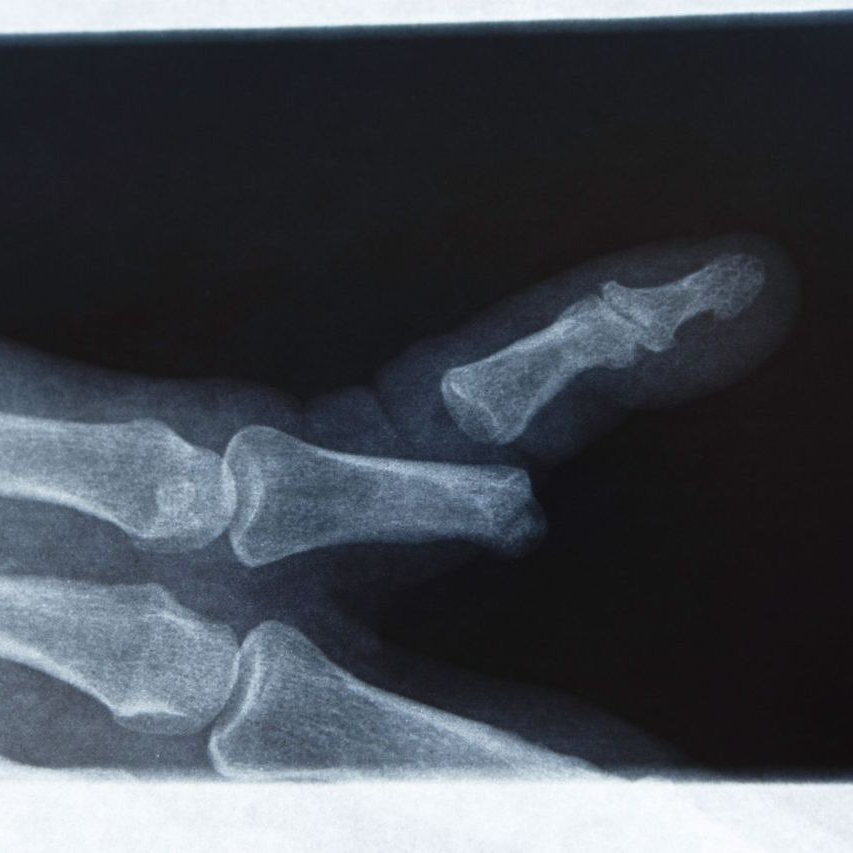

손가락 골절 완치기간

손가락 골절은 발가락과 비교했을 때 체중 부하가 없다는 점에서 회복이 상대적으로 빠른 편입니다.

그러나 손가락은 정교한 관절 움직임과 미세한 기능 수행이 중요하기 때문에, 단순한 회복 기간보다 기능 회복 여부가 더 중요하게 평가됩니다.

손가락 골절의 평균적인 완치기간은 다음과 같이 정리할 수 있습니다.